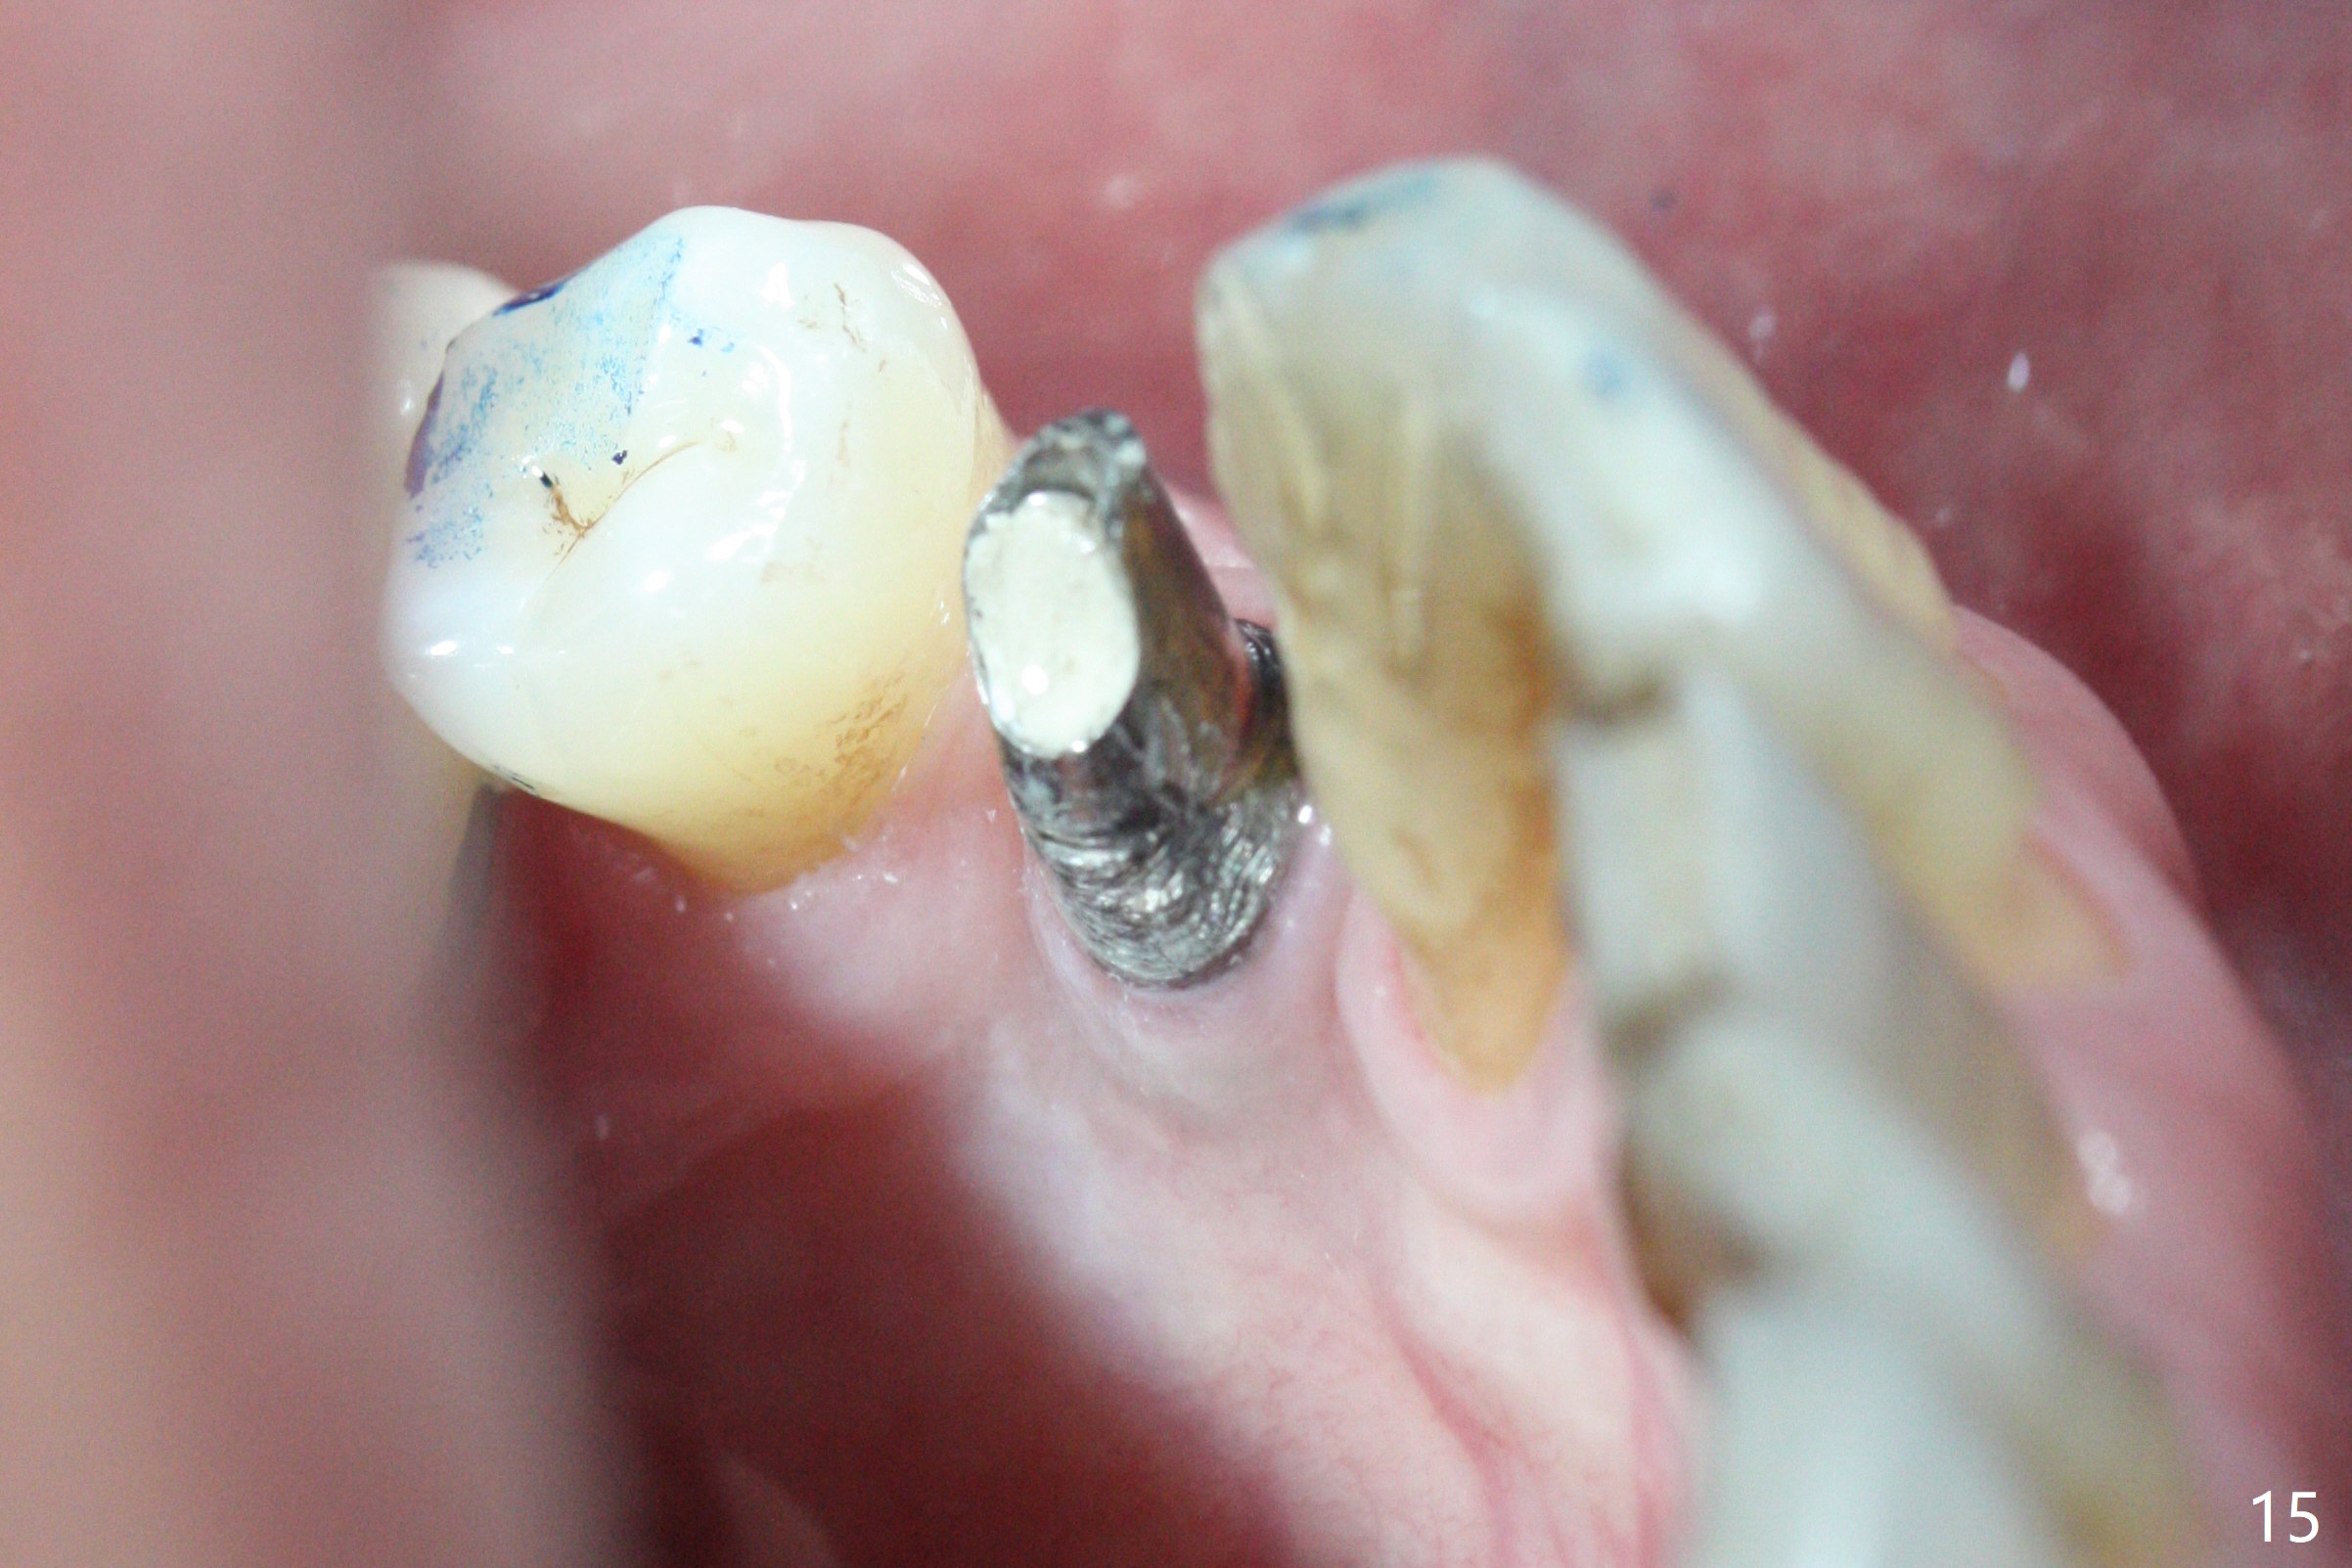

The residual root at #21 seems to be buccally positioned (Fig.1 *).  The initial osteotomy is established with the 1.6 mm drill at 11 mm (Fig.2).  Later the depth increases to 13 mm.  The initial osteotomy is found to be too lingual, but experience shows that as osteotomy increases in diameter, the trajectory would shift buccally due to the thick lingual plate (slope).  When 3.3 mm Magic drill reaches 11 mm, the patient feels pain.  It is probably due to the dense bone.  A 4x11 mm IBS implant cannot be seated due to high torque; it is removed.  The osteotomy is increased with 3.8 mm drill.  The implant is re-seated with >55 Ncm; it is over-lingually placed.  Due to failure to seat the implant driver completely, the implant cannot be un-torqued.  A 4.5 mm 15° angled abutment (3 mm cuff) is placed for immediate provisional (Fig.3,4 *).

The implant seems to have osteointegrated 4 months postop (Fig.9).  When a permanent crown is fabricated, it should have normal occlusal and buccal contour (from Fig.11 (provisional) to 12 red and black curved lines) as well as the buccal cervical extension (Fig.12 to cover the buccal gingiva (Fig.10 *).  If the lingual margin of the abutment is too prominent, return the case and the abutment will be changed to the one with 2 mm cuff (existing 3 mm).  The lingual margin of the abutment will be trimmed.  The patient is not pleased with the short buccal margin of the crown after cementation (Fig.13).  In fact the provisional should have been fabricated so that the its buccal margin should be subgingival and within the gingival outline.  It may prevent buccal plate collapse.  In fact the crown dislodges 1 year post cementation.  The lingual margin is prep lower to increase the abutment height.  Impression is taken.  Although the access hole is unnecessary for cementation, it acts as an escape hole so that there is no excess cement cervically (Fig.14-18).